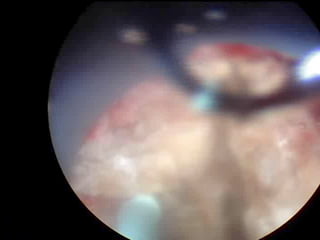

O documento discute o tratamento de urolitíase, especificamente a remoção de cálculos renais através de nefrolitotripsia. A cirurgia aberta é agora muito restrita devido aos avanços da ESWL e procedimentos endourológicos menos invasivos como ureteroscopia e cirurgia percutânea. A cirurgia laparoscópica está substituindo a cirurgia aberta como técnica menos invasiva que combina a tecnologia endourológica com a laparoscópica preservando